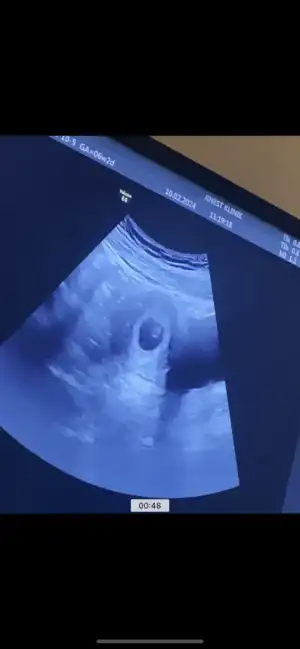

Yarın sabahtan bebeğimi görmeye gidecektim örneğin gitmeyeceğim ertesi güne aldım, iki işin arasına sıkıştırayım diye. Neyse hakkımızda hayırlısıBilmez miyim canım 5 sene en ağır mobbinglere maruz kalan biri olarak seni çok iyi anlıyorum istfanın eşiğine bile g3lmiş tim.Allah bu insanlara hidayet versin yola getirsin inşallah